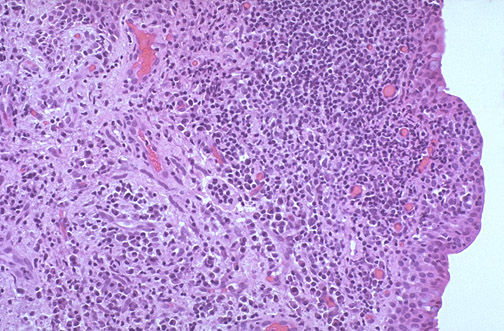

| This is the microscopic appearance of a chalazion of the eyelid. Note the intense chronic inflammation. Release of lipid from the Meibomian glands can result in a foreign body granulomatous inflammatory response. Thus, epithelioid macrophages as well as giant cells can be present. |